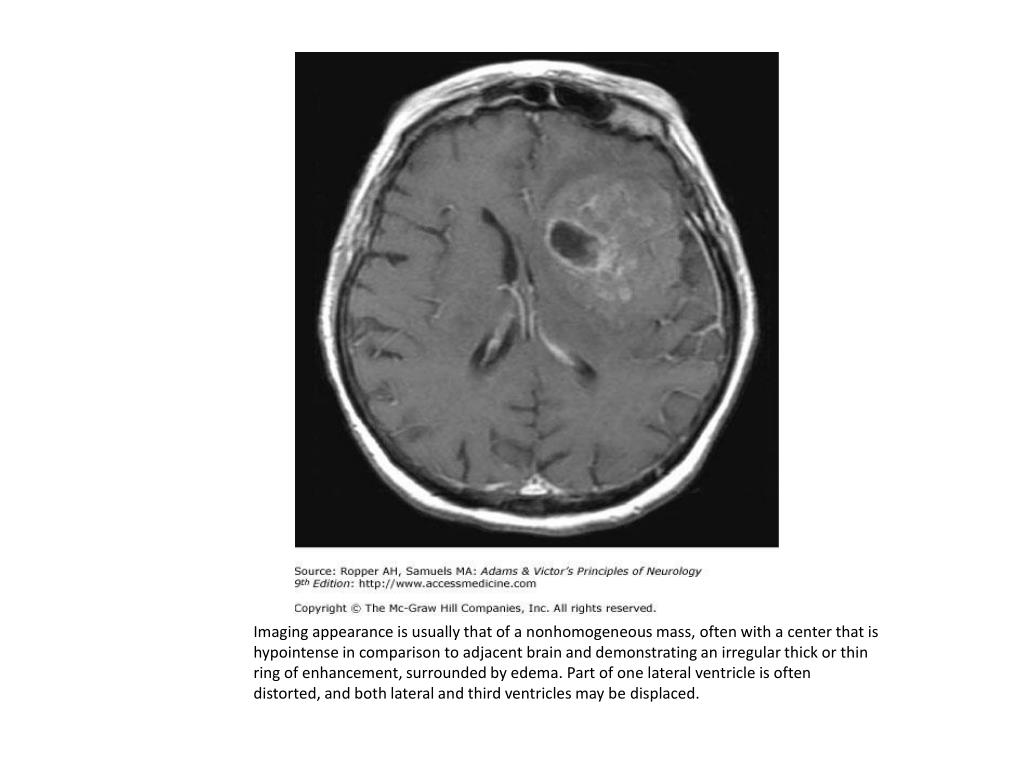

15. Imaging appearance is usually that of a nonhomogeneous mass, often with a center that is hypointense in comparison to adjacent brain and demonstrating an irregular thick or thin ring of enhancement, surrounded by edema. Part of one lateral ventricle is often distorted, and both lateral and third ventricles may be displaced.

14. MRI (Magnetic resonance imaging — Gadolinium-enhanced magnetic resonance imaging (MRI) is usually the only test needed to suggest a brain tumor. MRI may also provide information that indicates the specific tumor type. • Malignant gliomas are typically hypointense on T1-weighted images, and enhance heterogeneously following contrast infusion. Enhancing tumor can be distinguished from the surrounding hypointense signal of edema on T1-weighted sequences. • In eloquent areas of the brain, imaging after activation of sensory and motor areas by appropriate stimuli may permit separation of tumor from normal brain preoperatively